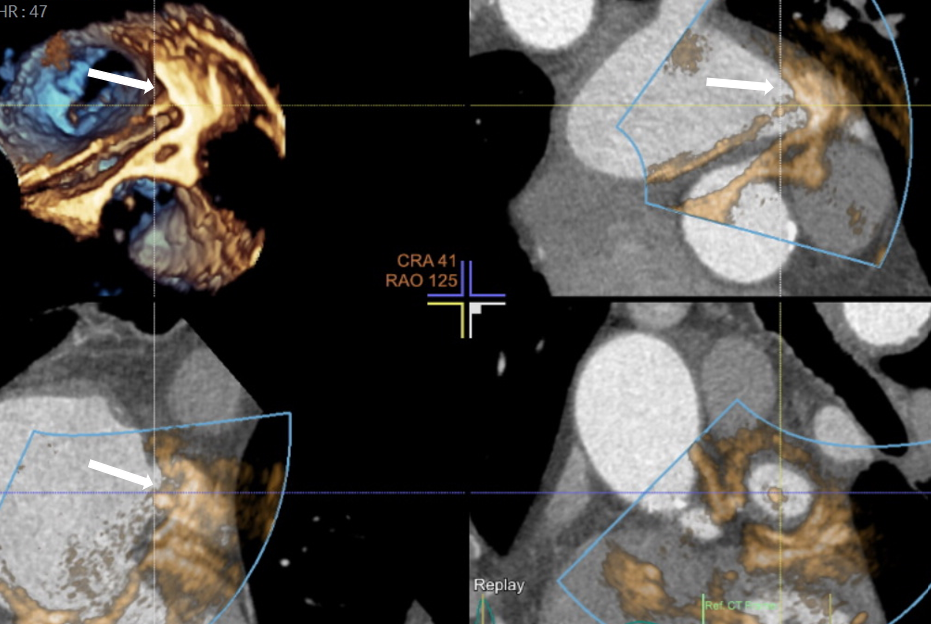

Skopia rentgenowska – zakontrastowane uszko lewego przedsionka

Kwalifikacja do zabiegów prowadzona jest na Oddziale Chorób Strukturalnych Serca, którego koordynatorem jest prof. Marcin Fijałkowski z I Katedry i Kliniki Kardiologii GUMed. Kluczową rolę w planowaniu zabiegów odgrywa echokardiografia przezprzełykowa i tomografia komputerowa serca. Szczegółową analizą obrazów tomografii komputerowej zajmuje się prof. Edyta Szurowska kierująca II Zakładem Radiologii GUMed oraz dr Dorota Kulawiak-Gałąska z Zakładu Radiologii naszego Uniwersytetu.